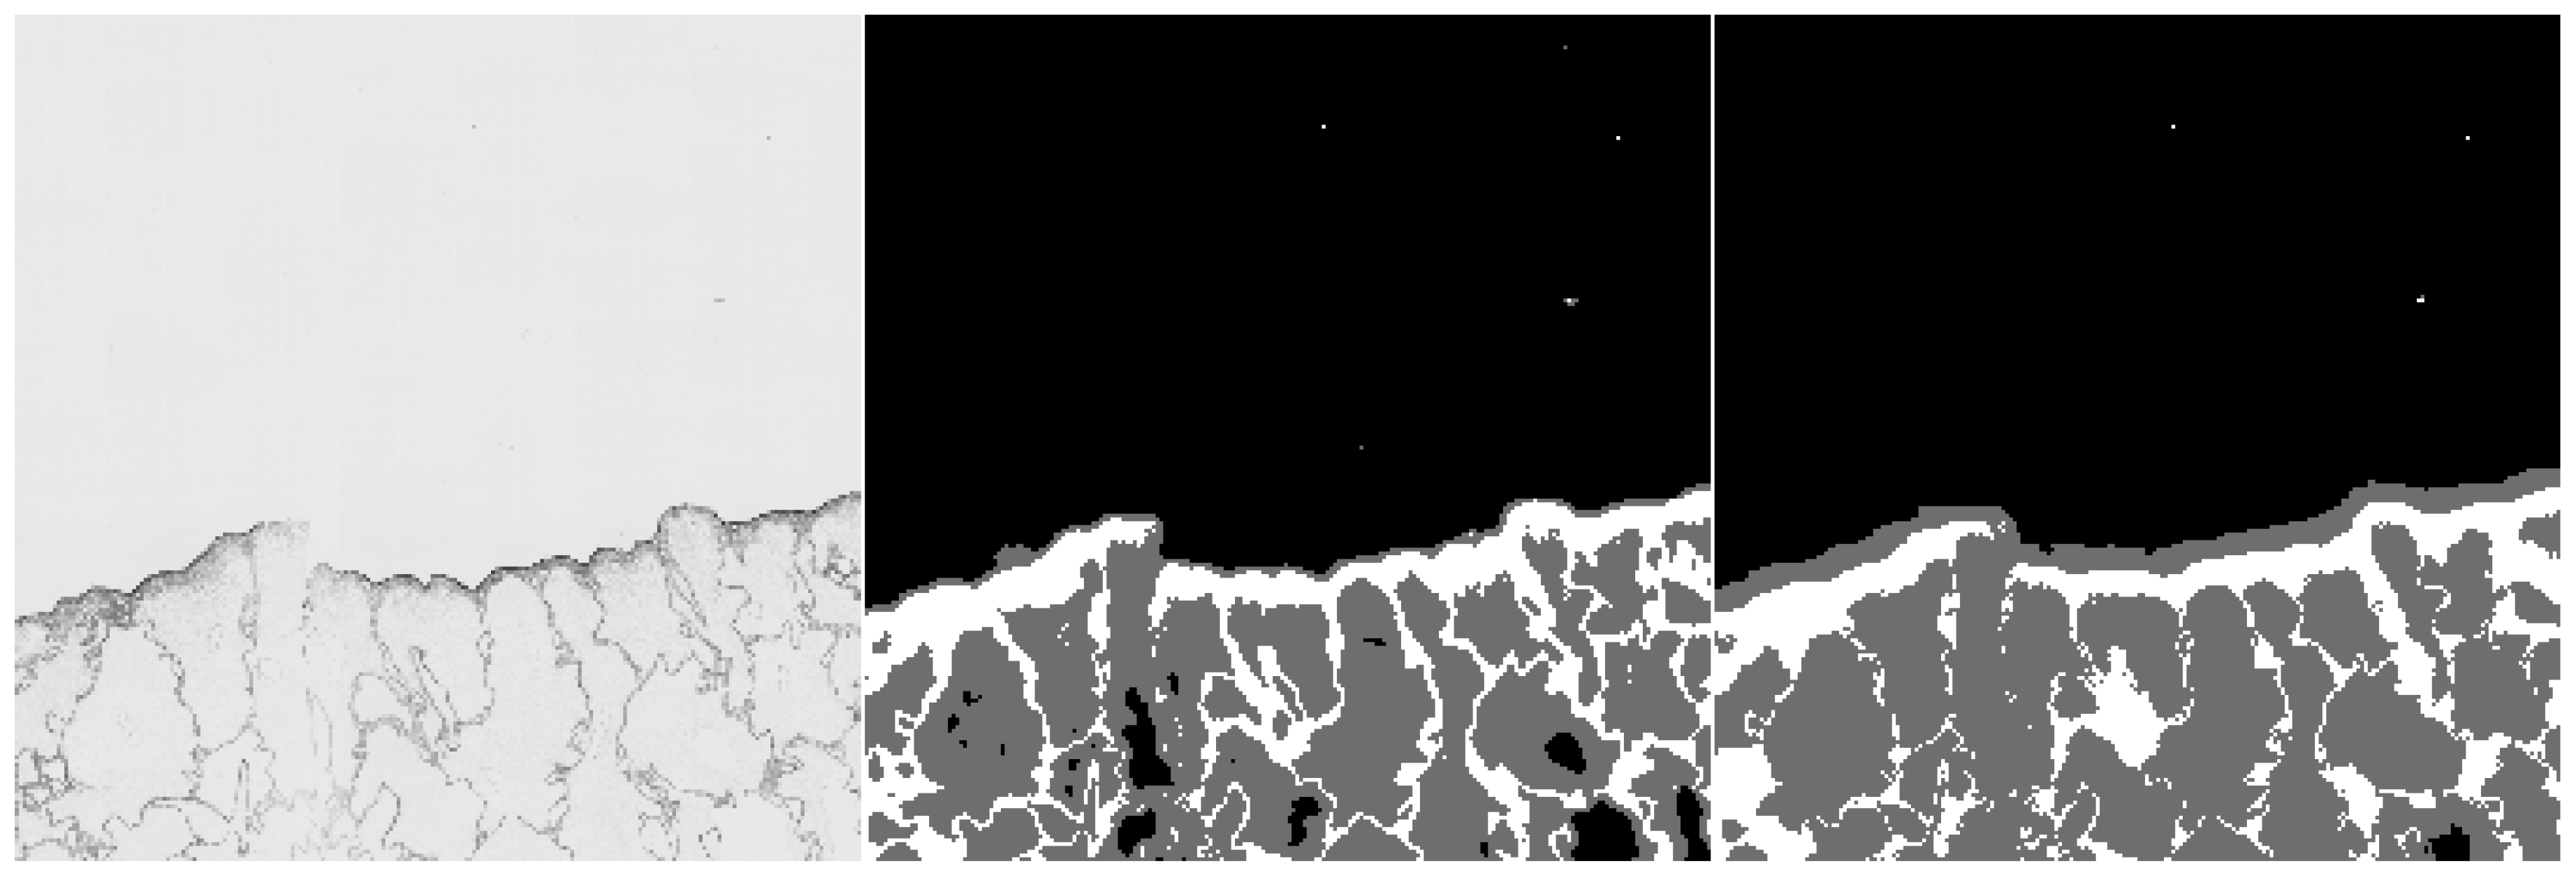

- We introduce a two-stage method for semantic segmentation of liver scaffold hematoxylin-eosin (H&E) stained section images. In the first stage, we train the Naive Bayes classifier on simple texture descriptors. In the second stage, we utilize the classifier’s outputs as training data for U-Net-based convolutional neural network.

- We compare the single-stage approach with the two-stage method on a small subset of manually annotated data with the two-stage method reaching superior results.